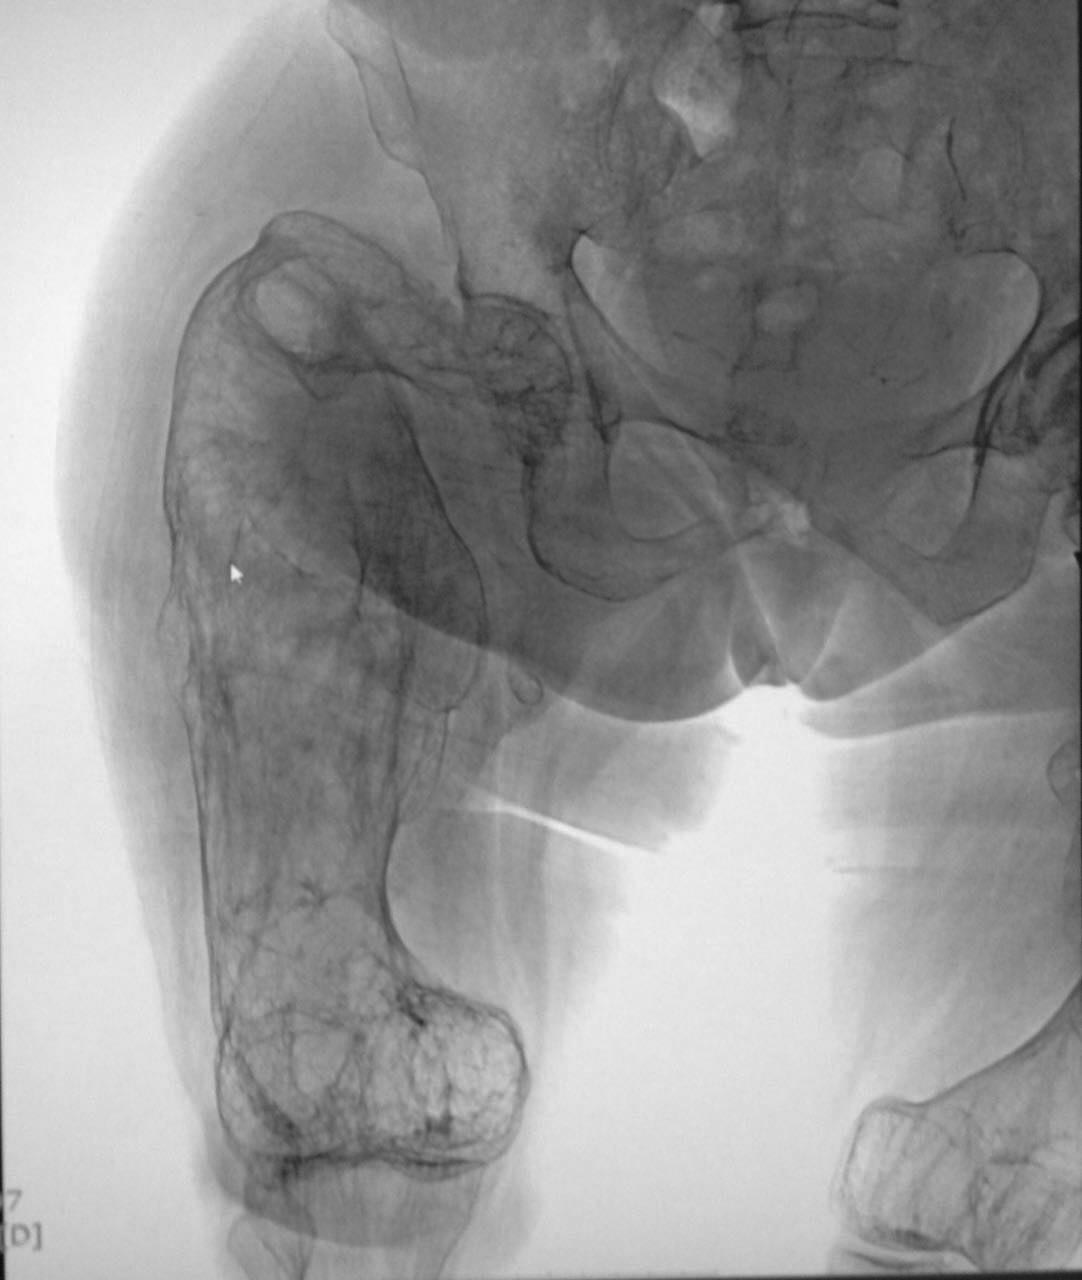

Пациентка Н. 1940 года рождения поступила в стационар по экстренным показаниям с предварительным диагнозом: Закрытый перелом шейки правой бедренной кости на фоне

выраженного дегенеративно-дистрофического изменения правой бедренной кости. Выраженный болевой синдром. Стенокардия напряжения ФК 2. Гипертоническая болезнь 3 ст., риск 4. ХСН 1. Со слов упала с высоты своего роста за 2 дня до поступления.

Из анамнеза: в детстве была обычным ребенком, развитие по возрасту. Работала полировщицей на заводе, работа связана с вибрацией. Со слов пациентки появились боли области бедер и ТБС с 1984г, далее присоединились ограничения в движениях тазобедренных суставах. в 2006, 2007, 2009гг патологические переломы бедренных костей на уровнях с/3 и шейки. Перенесенные заболевания: гипертиреоз.